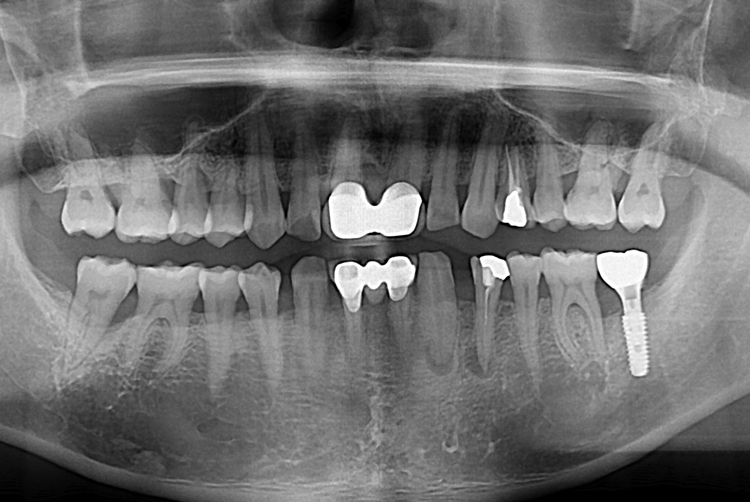

[임플란트] 어금니 임플란트

치료전 : 2017-02-08

세종치과는 많은 환자와 다양한 케이스를 바탕으로

항상 편안한 임플란트 수술을 제공하고자 노력하고,

오래동안 튼튼히 쓸 수 있는 임플란트 수술을 가장 큰 목표로 삼고 있습니다.